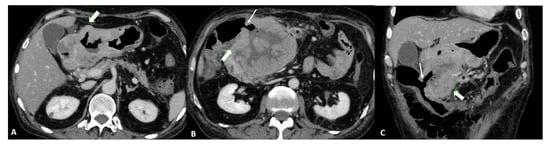

Finally, T4a also demonstrates serosal involvement, which makes the differential with T3 very difficult. This is especially true because the gastric serosa is not well defined due to the different amounts of subserosal adipose tissue. To solve the differential, T4a frequently shows solid nodules or band-like stranding in the perivisceral adipose tissue (Figure 4).

Figure 4.

(A) Axial 2D image in the portal venous phase of a T4a gastric cancer in a 66-year-old female patient. The tumor (thick arrow) is the enhanced wall thickening in the lesser curvature side of the middle body of the stomach which penetrates the serosa with some solid deposits (white asterisk) in the perivisceral fat tissue and some pathologic lymph nodes (thin arrow) with necrotic-colliquative components inside. (B) Axial 2D image of a T4a gastric cancer in a 78-year-old female patient. The tumor (thick arrow) is the enhanced wall thickening on the lesser curvature side of the low body of the stomach which penetrates the serosa with some spiculatures in the perivisceral fat tissue and a pathologic lymph node (black asterisk).

T4b shows extension into an adjacent structure and shows the loss of the fat plane between the gastric mass and adjacent organs (Figure 5).

Figure 5.

T4b gastric cancer in a 74-year-old female patient. (A,B). Axial 2D images in the portal venous phase and (C) Coronal multiplanar reconstruction showing (thick arrows) a bulky tumor of the middle-low body of the stomach and of the gastric antrum with necrotic-colliquative components inside, ulcerative alterations and some solid deposits (black asterisks) in the perivisceral fat tissue. The tumor fistulizes and infiltrates the transverse colon (thin arrows).